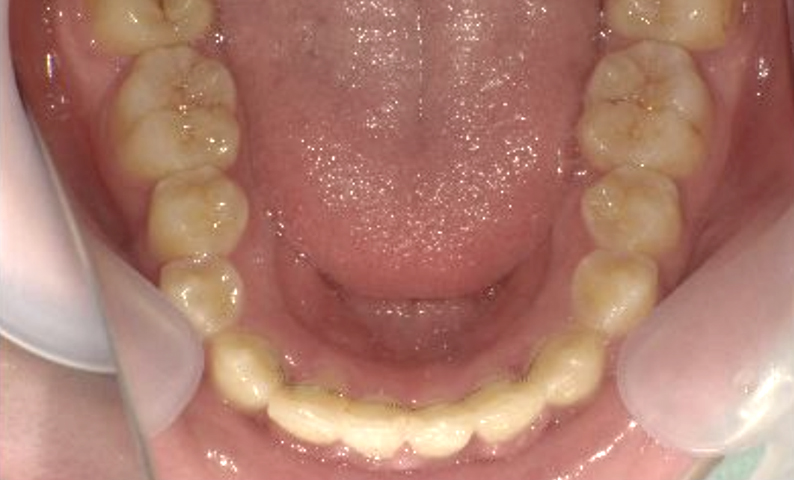

症例_001 下顎だけの部分矯正

治療期間:6ヶ月金額:27万円+税女性前歯のガタガタ下の前歯だけ

| Before | After |

|---|---|

|